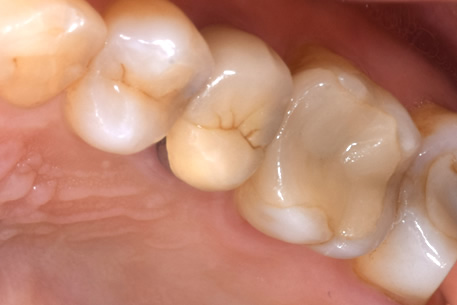

症例② CR

治療後

年齢 30代・男性

主訴 右上1番

治療内容 右上1番CR

治療費 右上1番CR:約1.500円(保険診療3割負担)

(2022年7月現在)

治療期間 1日

リスク・副作用 麻酔がきれた後に痛みがでる可能性がある。

治療方針 口蓋側近心から虫歯をとり、CR充填を行う。

特記事項 治療後痛みはでていない。

担当者所見 唇側には広がっていなかったので、審美的な問題はおきないと考えられる。